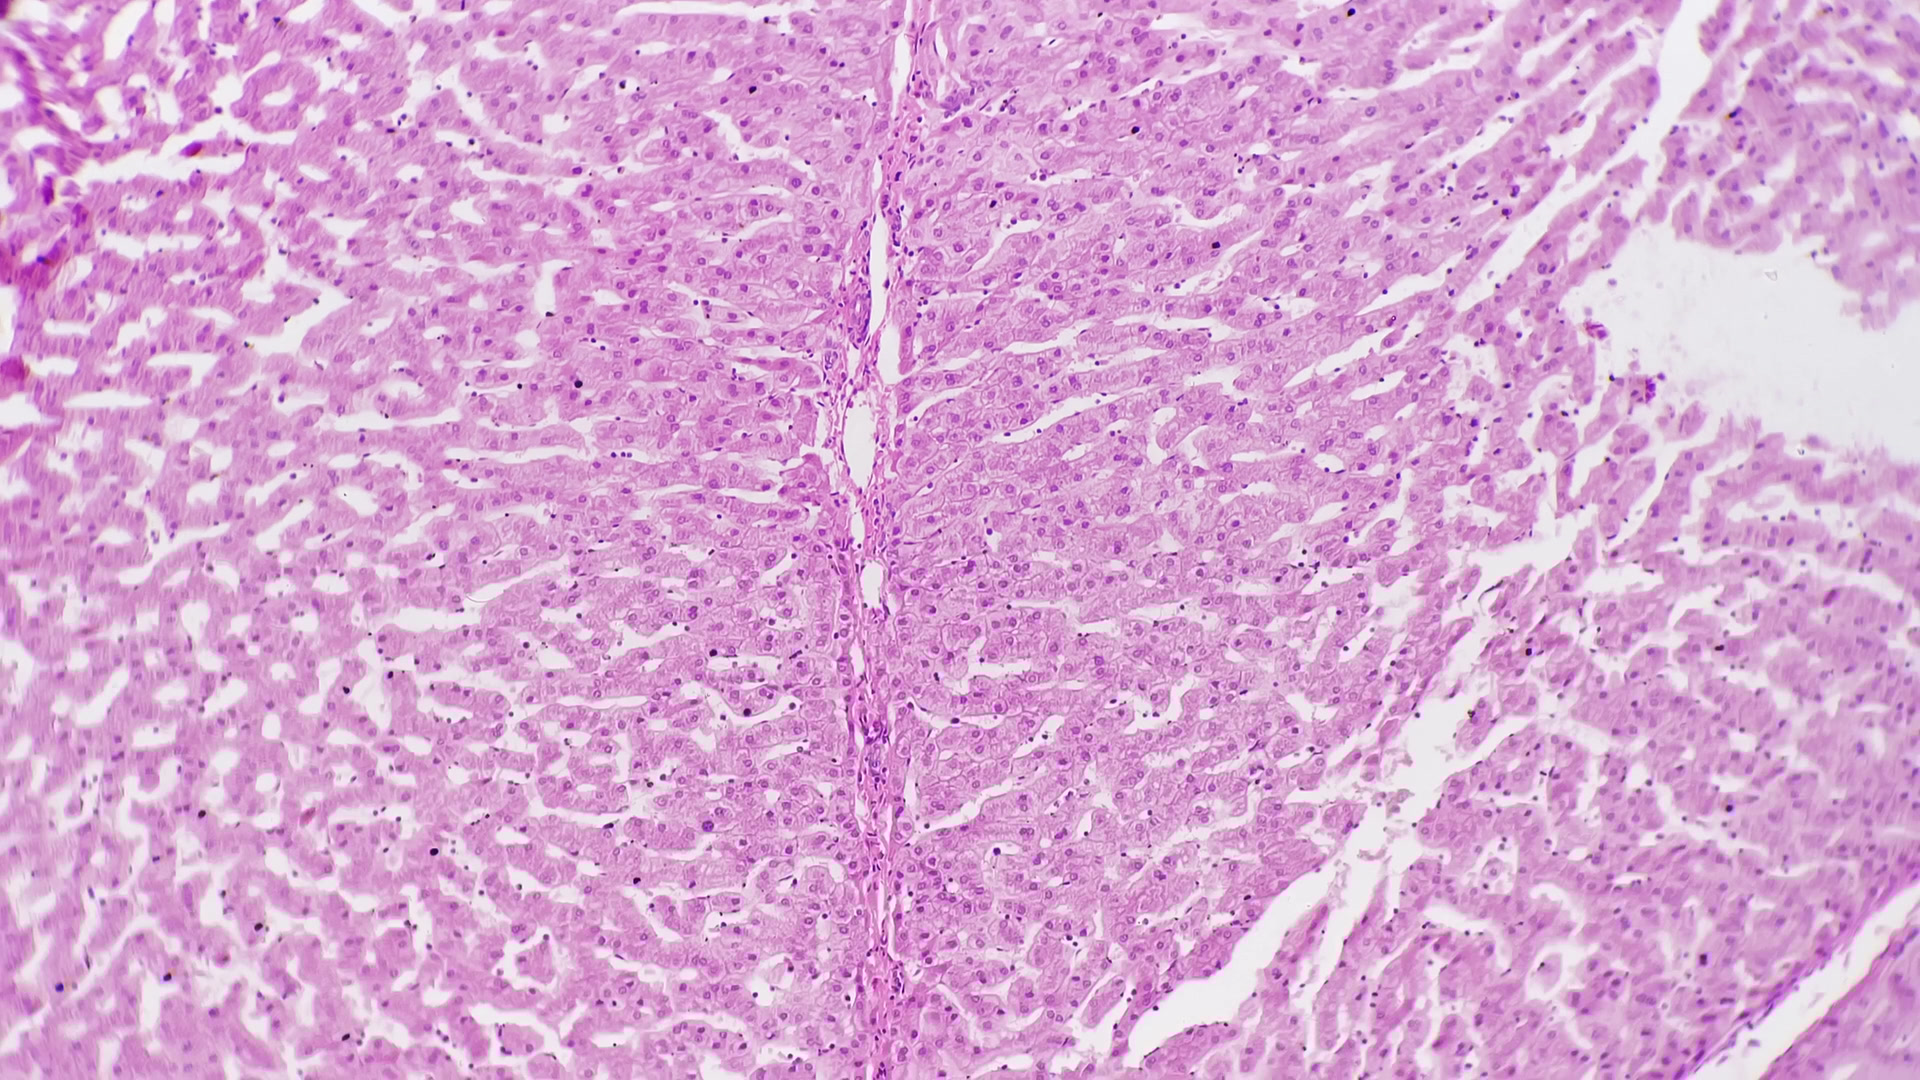

간이 안 좋을 때 나타나는 증상

간이 안 좋을 때 나타나는 증상은 간 기능 저하로 인해 여러 가지로 나타날 수 있습니다.

간이 안 좋을 때 우리 몸에서는 증상들이 나타납니다.

몇 가지나 해당하시는지 확인하시고 5가지 이상 되신다면 꼭 병원 가보시길 추천드립니다.